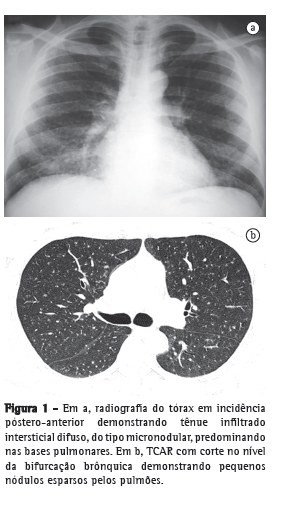

As manifestações pulmonares iniciaram-se em dezembro de 2008, com febre, tosse e episódios intermitentes de hemoptise de pequena monta. Recebeu tratamento antibiótico com amoxicilina (500 mg a cada 8 h por 7 dias), apresentando melhora da febre e da hemoptise, mas manteve a tosse seca. Negava outros sintomas, como emagrecimento, sudorese noturna ou piora do estado geral. Foi encaminhado para o setor de pneumologia para investigação. O exame físico não demonstrou alterações significativas. A radiografia de tórax revelou a presença de tênue infiltrado micronodular difuso (Figura 1a), melhor caracterizado pela TCAR de tórax (Figura 1b).

O aspecto radiológico mais comum é de opacidade alveolar associada a broncograma aéreo.(1) Relatos baseados em estudos tomográficos descrevem a presença de opacidades nodulares, opacidades em vidro fosco e pequenos nódulos com distribuição centrolobular, além do padrão de árvore em brotamento, abrindo um grande leque de possibilidades diagnósticas.(2)